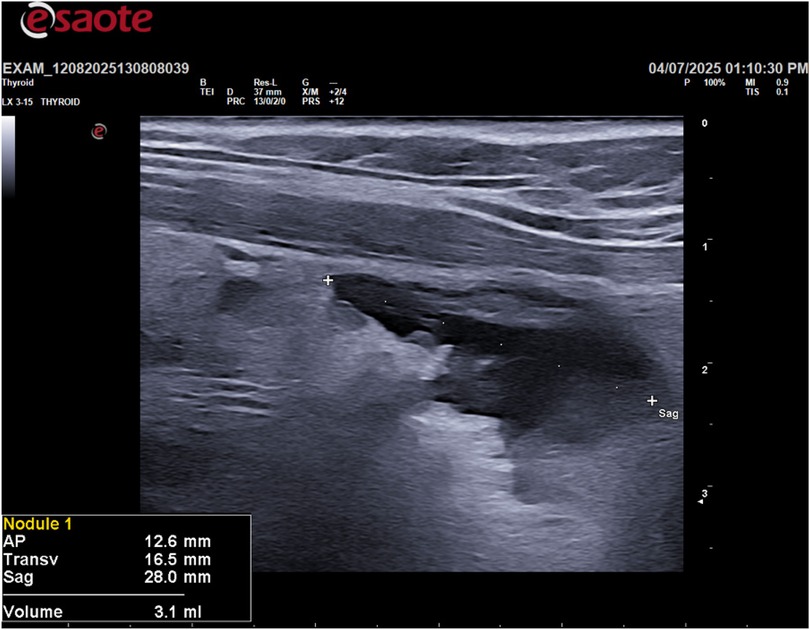

Following the ultrasound, an ultrasound-guided fine-needle aspiration (FNA) was performed on the cystic lesion (Figure 2). Approximately 90 ml of clear, “rock water"-colored fluid was aspirated (Figure 3). The cyst has been completely drained: AP 12.6 mm, Transverse 16.5 mm, and Sagittal 28 mm, for a calculated volume of 3.1 ml (Figure 3). The aspirated cystic fluid was immediately sent for biochemical analysis.

Figure 3

Ultrasound image of a thyroid, displaying a nodule labeled \

Figure 3. Post fine-needle aspiration (FNA) ultrasound image.